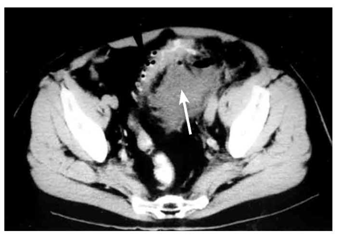

- טומוגרפיה ממוחשבת (CT) - מראה את הסעיפים עם בועות האוויר שבתוכם (תצלום 13.6) . בדלקת הסעיפים אפשר לראות כרכשת מעובה, ומורסות במקרה של התנקבות המוגבלת על-ידי האיברים שבסביבה. בחולים שהודגמו בהם מורסות, ניתן להחדיר מחט המונחית על-ידי טומוגרפיה ממוחשבת למורסה ולנקזה, ולאחר מכן להשאיר נקז להמשך הניקוז.

סיבוכי דלקת סעיפי הכרכשת ודלקת הצפק

האבחנה היא בטומוגרפיה ממוחשבת או באולטרה-סאונד שבהם אפשר להדגים את המורסה ולראות את המעי המעובה, חסר המבנה השקי (סקולרי) (תצלומים 14.6ו- 15.6).